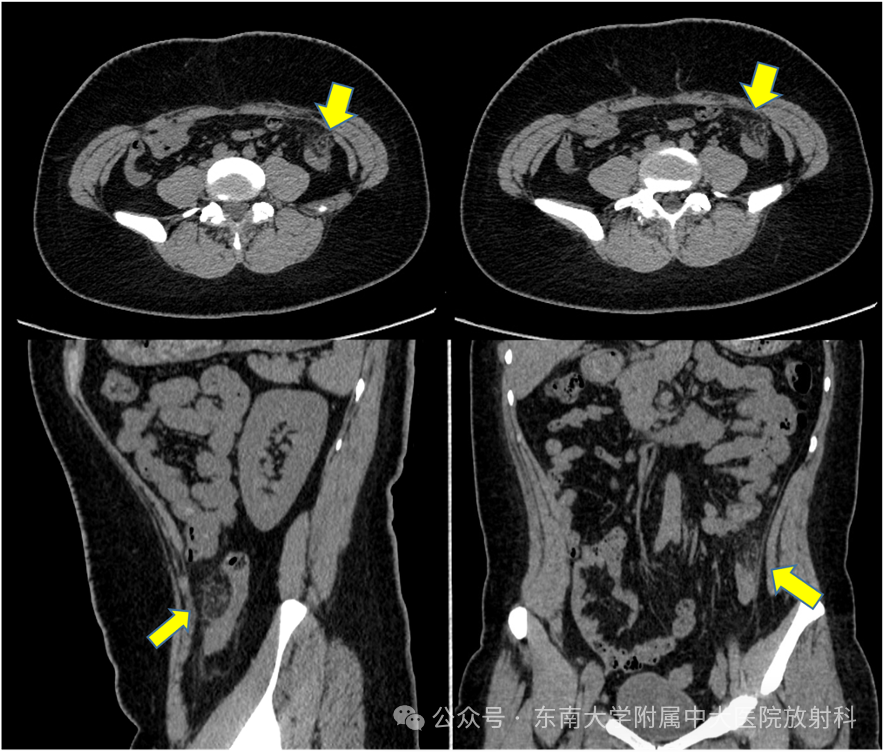

消化系统疾病——肠脂垂炎